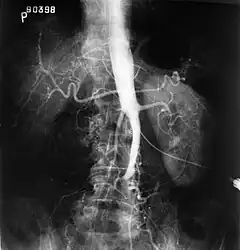

-

Plate from Gray's Anatomy showing the abdominal aorta and the common iliac arteries. -

Fluoroscopic image of an affected aorta

The physical examination usually shows weakened femoral pulses and a reduced ankle-brachial index. The diagnosis can be verified by color duplex scanning, which reveals either a peak systolic velocity ratio ≥2.5 at the site of stenosis and/or a monophasic waveform. MRA and multidetector CTA are often used to determine the extent and type of obstruction. Another technique is digital subtraction angiography which allows verification of the diagnosis and endovascular treatment in a single session.[8]

Angiography provides important information regarding the perfusion and patency of distal arteries (e.g. femoral artery). The presence of collateral arteries in the pelvic and groin area is important in maintaining crucial blood flow and lower limb viability. However, angiography should only be used if symptoms warrant surgical intervention.[8]